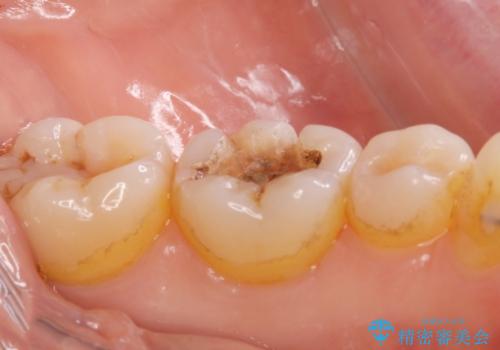

- 過去に治療した銀の詰め物が取れて来院された患者様です。

詰め物のやりかえをするのなら白い詰め物でやりかえたいとのことなのでe-maxインレーでの治療を行いました。